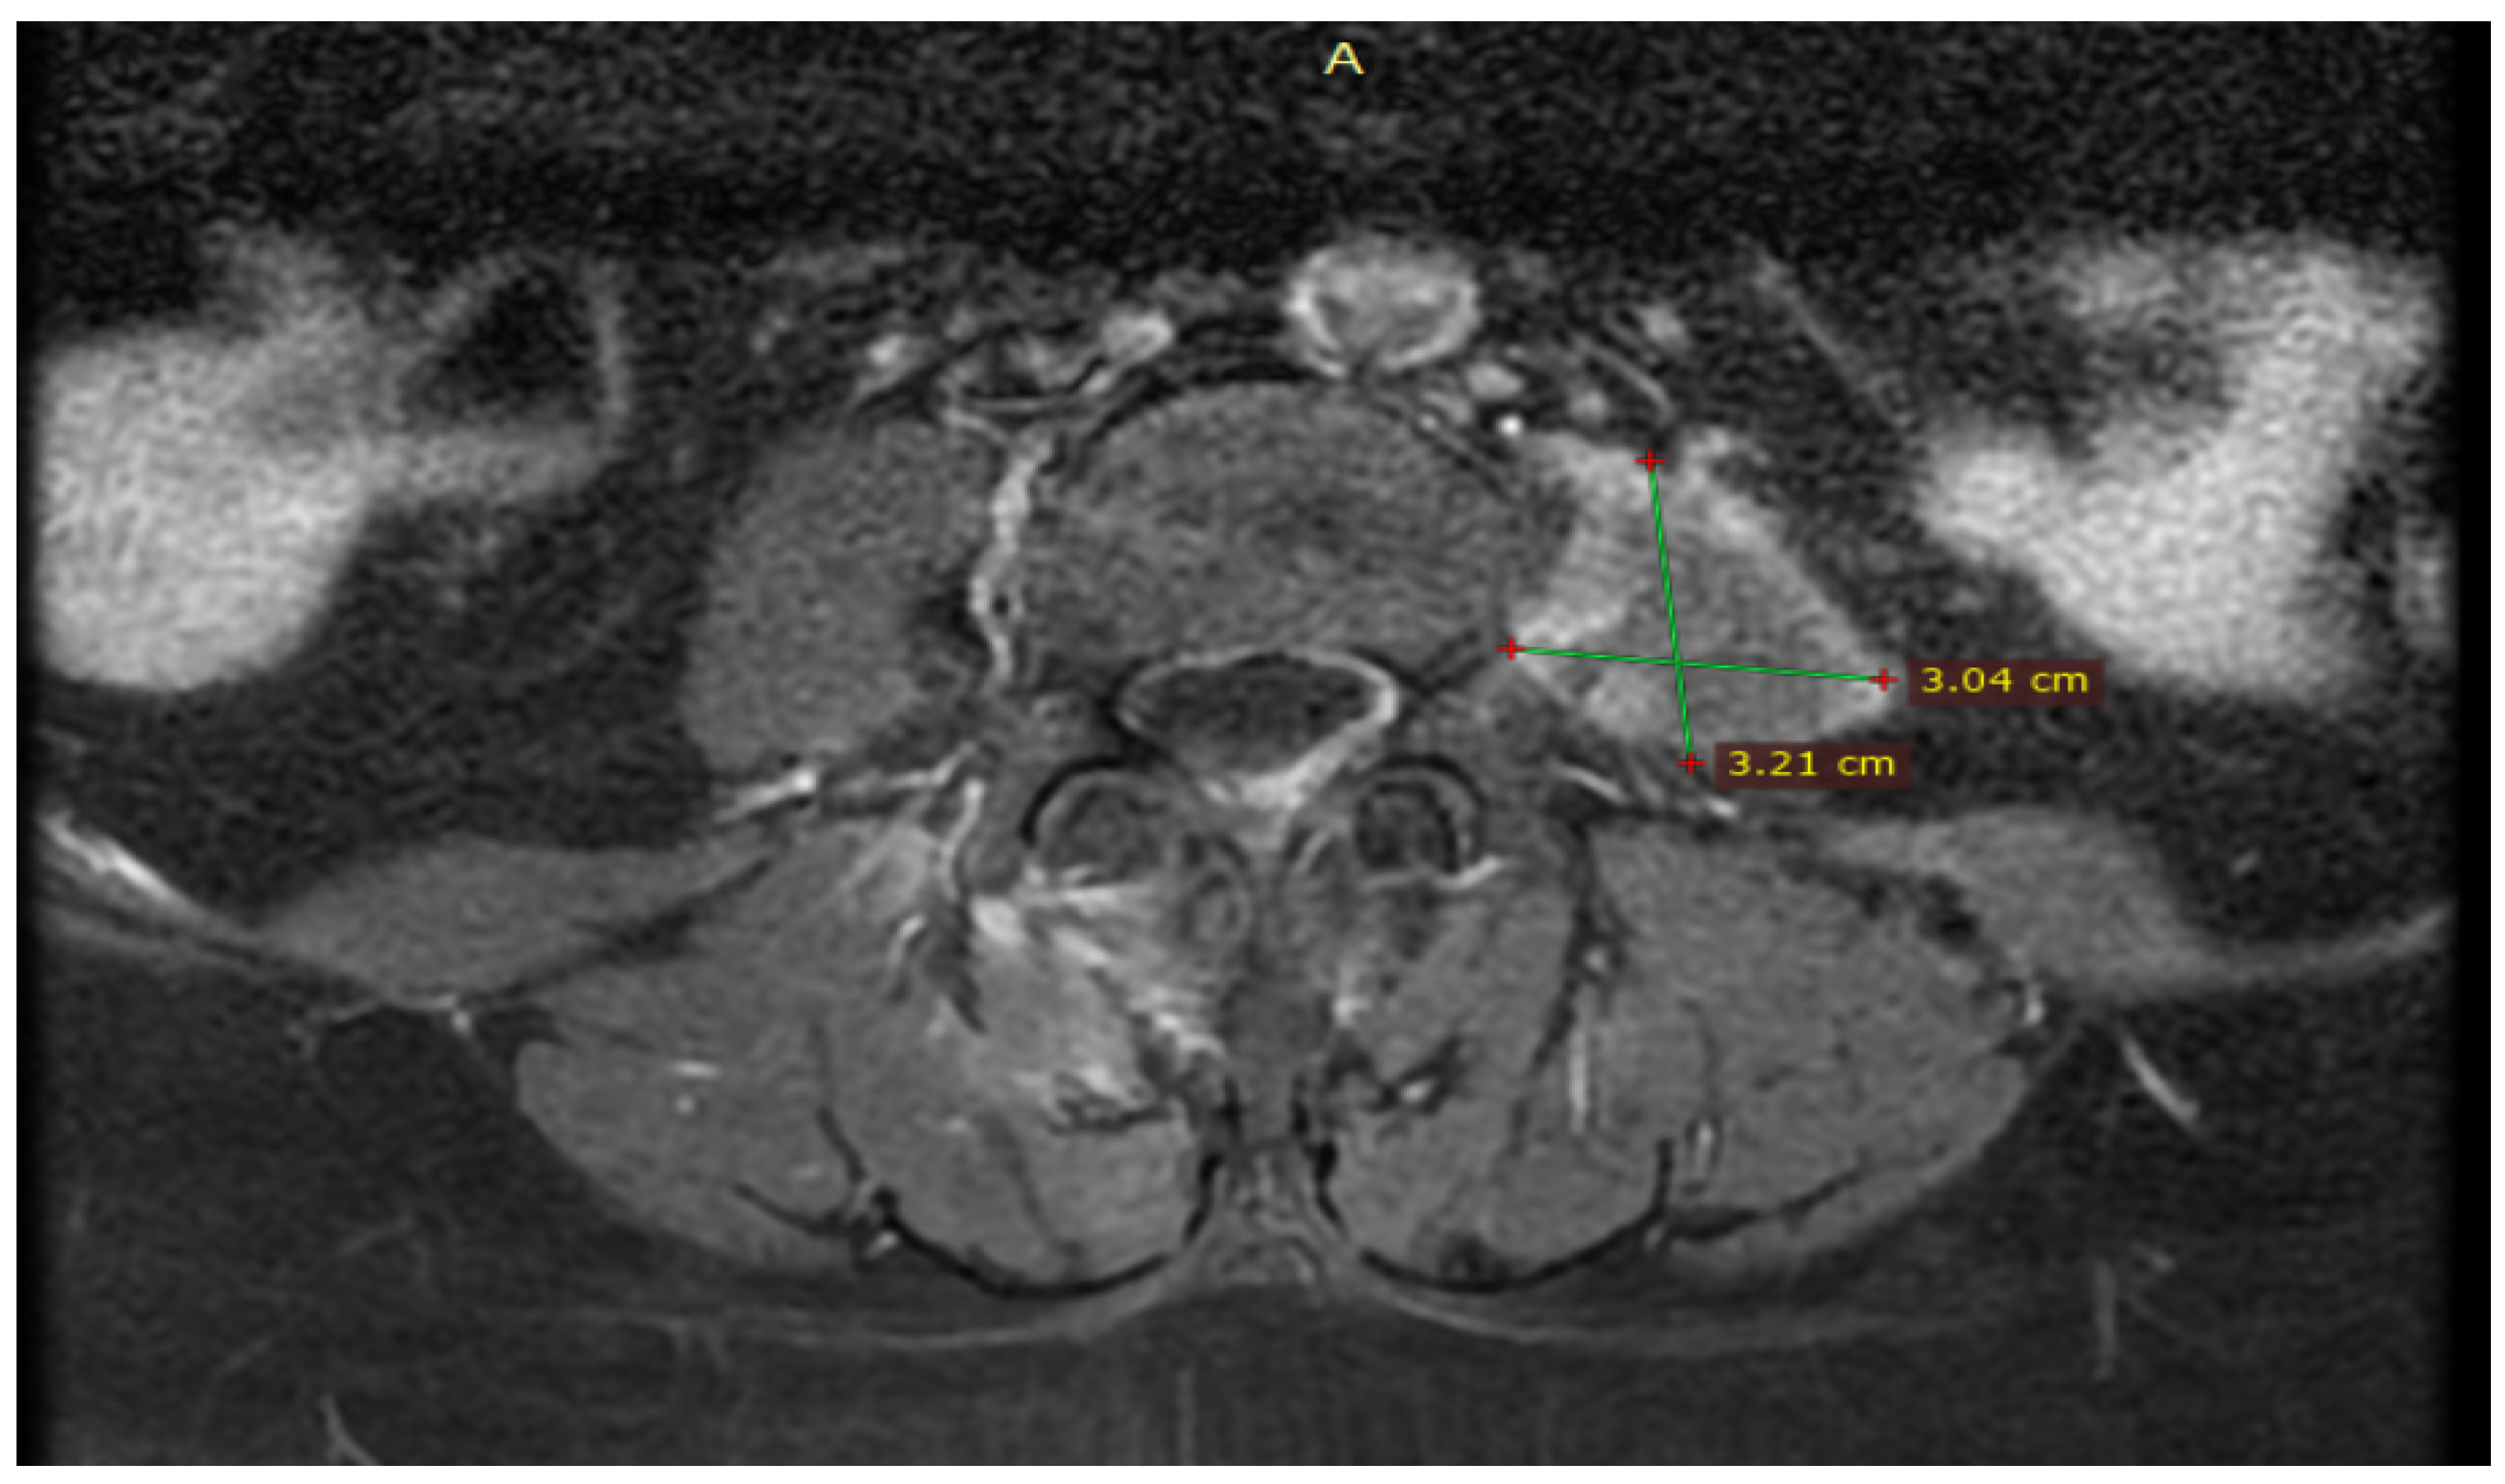

During hospitalization, she was advised to have an elective laparoscopic cholecystectomy, which she declined. Because endoscopic retrograde cholangiopancreatography (ERCP) or magnetic resonance cholangiopancreatography (MRCP) cannot be performed in our hospital, she was offered to have these investigations performed in our primary county hospital, but she also delayed these investigations. At the reassessment after 31 days, the patient stated that she did not undergo any other ultrasound or blood test during this period due to the remission of symptoms and jaundice. She was again medically and clinically reevaluated in the Emergency Department in collaboration with the general surgeon, where no sign of infection was observed, and laboratory tests were in the normal range. Also, the magnetic resonance imaging (MRI) of the thoracic and lumbar spine performed in the 31 days did not identify a secondary cause for her left iliopsoas abscess (Figure 6).

Figure 6.

MRI of the thoracic and lumbar spine performed at 31 days reassessment showed evacuated abscess of the left iliopsoas muscle with minimal residual muscle inflammation.